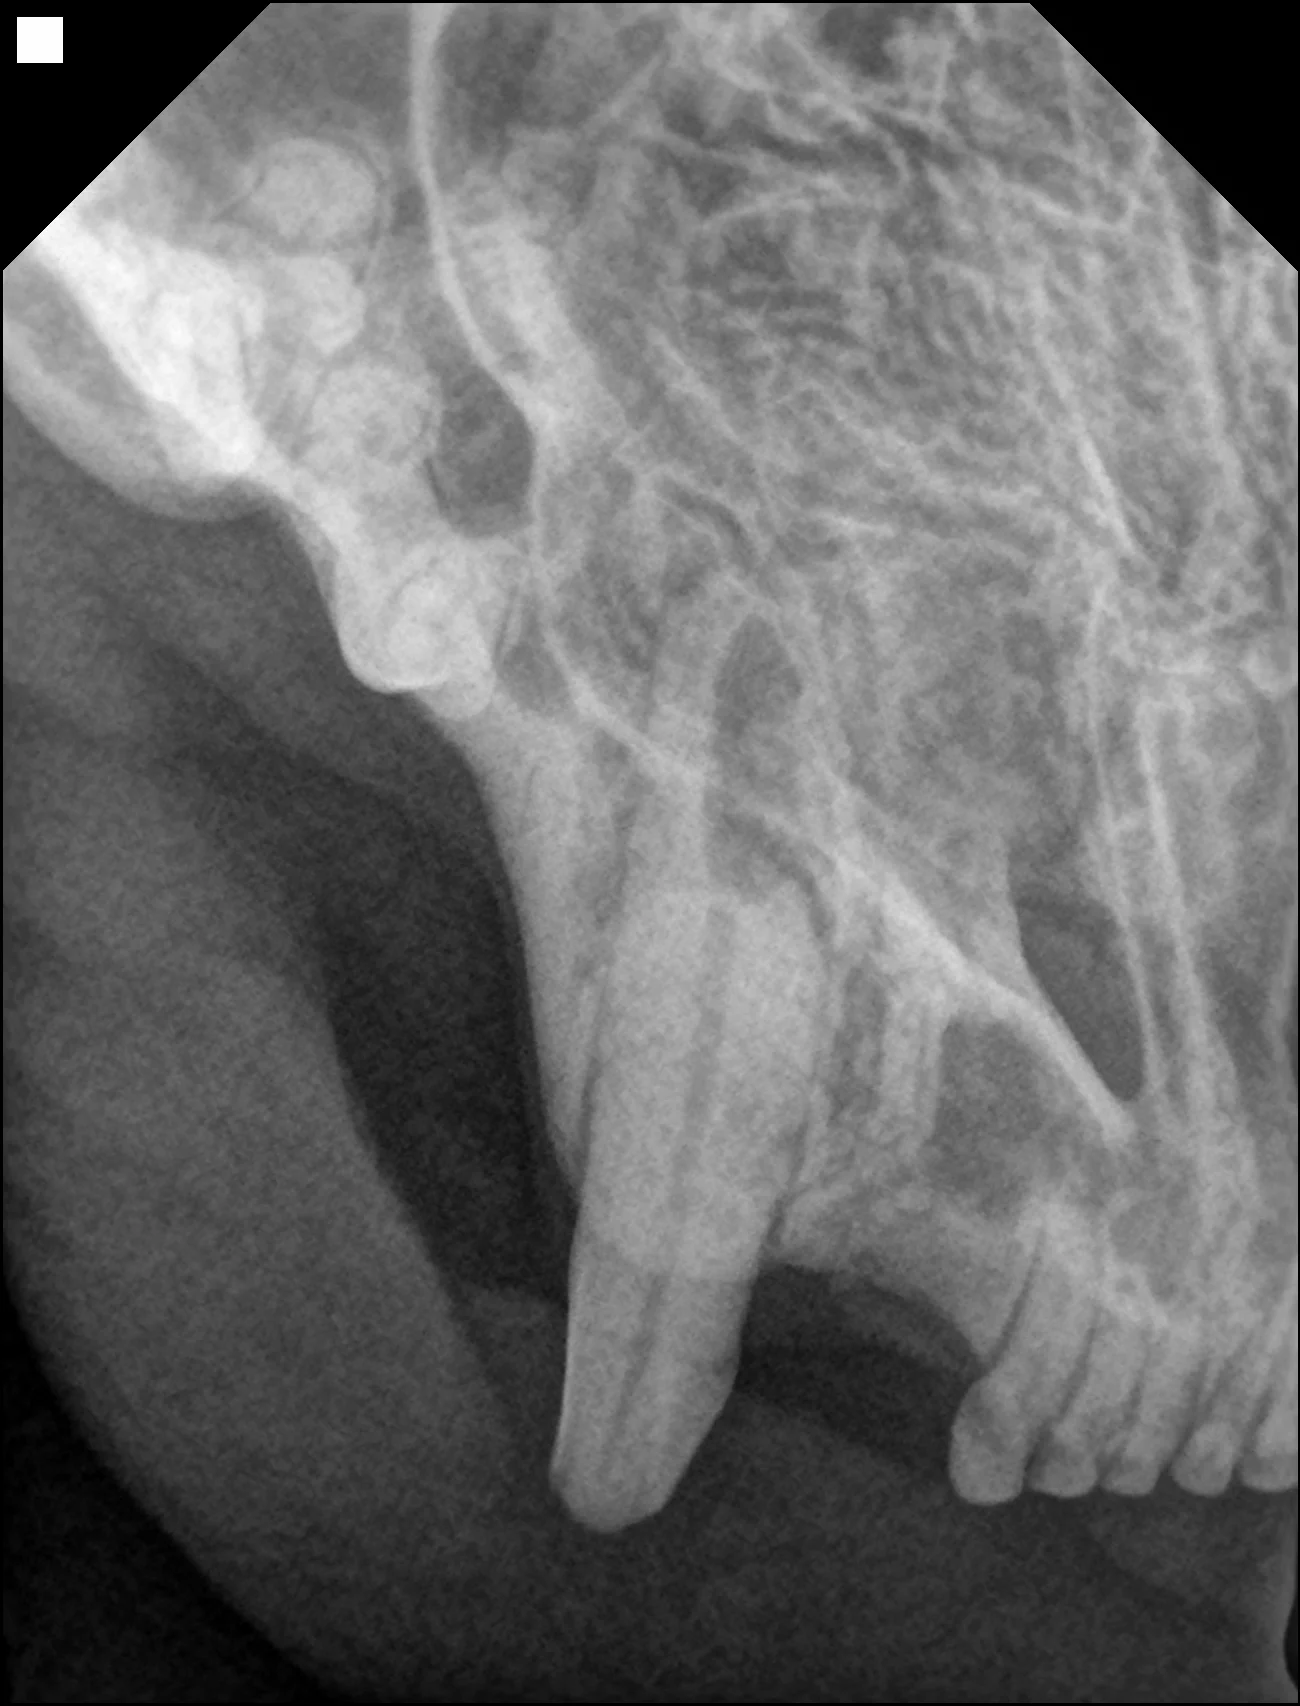

• 육안으로 문제가 없어 보이는 경우에도 치과방사선이나 Cone beam CT 촬영을 통해 치아 흡수성 병변이 확인되는 경우가 많습니다.

치아흡수가 치과방사선에서도 확인됨​

치과방사선으로 확인된 치아흡수